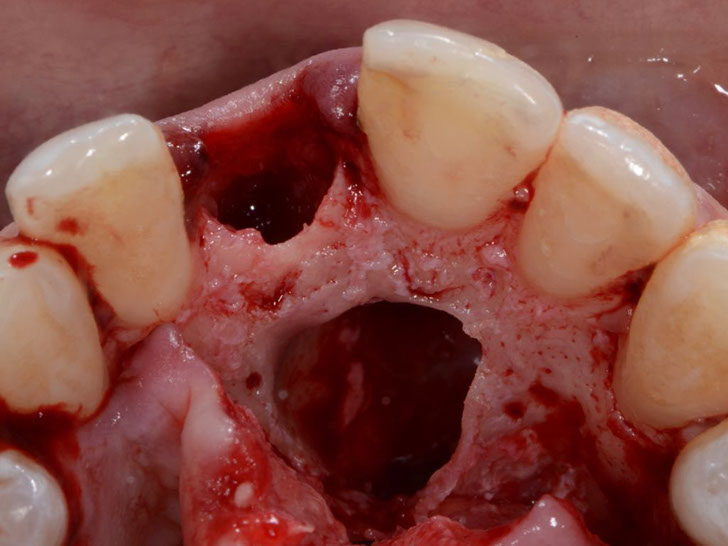

Dr. Alberto

Salgado